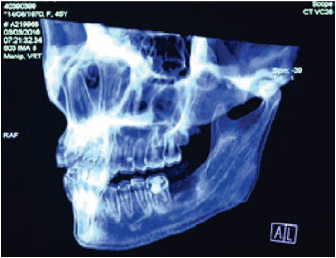

Clínicamente, se evidenciaba una deformidad en el contorno de la región del ángulo mandibular izquierdo. Intraoralmente, se observaba una lesión tumoral de 2,5 cm de alto por 2,7 cm de diámetro. Tomográficamente, estaba registrada una imagen hipodensa en la zona del segundo molar inferior izquierdo, con una expansión de cortical a vestibular y lingual ipsilateral (figuras 2 y 3). Radiográficamente, en la zona periapical del segundo molar inferior izquierdo, se observó un ensanchamiento del espacio del ligamento periodontal, sin causa aparente, con pérdida ósea perirradicular (figura 1). La paciente refirió que un año atrás, aproximadamente, se le había realizado una exodoncia del tercer molar inferior izquierdo, sin complicaciones, concomitante con el crecimiento de dicha lesión. Posterior a la evaluación, los servicios de Cirugía Plástica, Maxilofacial, Cabeza y Cuello realizaron una junta médica, donde se tomó la decisión de llevar a cabo una mandibulectomía segmentaria con reconstrucción de colgajo microvascularizado de cresta iliaca y vaciamiento ganglionar cervical ipsilateral.